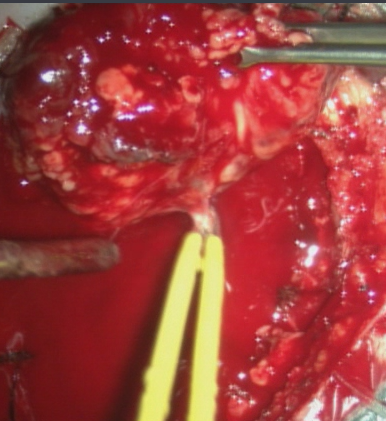

介入手术完成后,行开颅手术治疗。可直接切断经颈外动脉对瘤体的供血。

沿着肿瘤边缘分离肿瘤。

术中出血约1500ml.

完整切除肿瘤。

手术用时3小时55分钟.完整切除肿瘤。